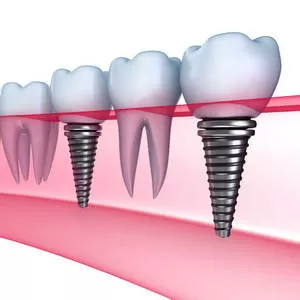

Имплантация зубов — это хирургическая операция по вживлению в челюсть искусственного корня (импланта), на который впоследствии устанавливается абатмент, а затем коронка или протез. Это дорогой, но лучший способ восстановить зубы. Дорогие шведские имплантанты (Astra Tech, Nobel, Straumann) служат 30-40 лет и дольше, в зависимости от ухода. Израильские импланты (например Alpha Bio) подешевле и срок эксплуатации меньше в 2 раза. Перед обращением к стоматологу-имплантологу рекомендуем узнать из наших статей о противопоказаниях к процедуре, прочитать о методах, а также подробнее познакомиться с применяемыми моделями имплантатов.

- Установка имплантантов зубов (зубных имплантов)

- Какие бывают виды зубных имплантов в стоматологии